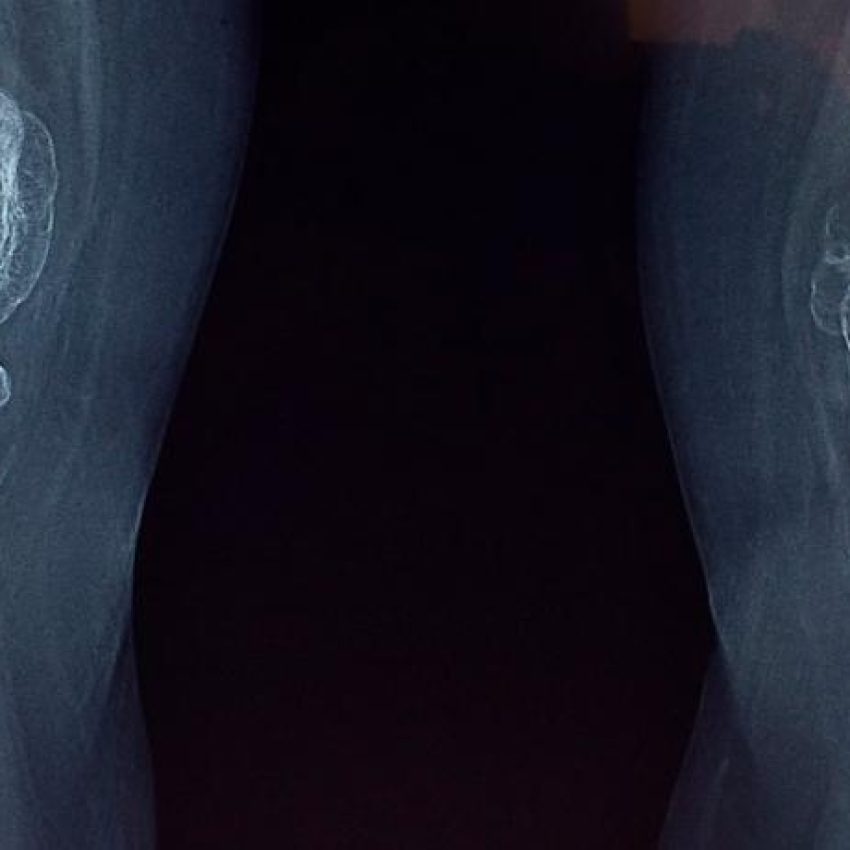

Nuestros traumatólogos utilizan técnicas avanzadas de imagen, como radiografías, resonancias magnéticas y tomografías computarizadas, para diagnosticar con precisión las lesiones traumáticas y diseñar un plan de tratamiento adecuado que puede incluir desde manejo conservador hasta cirugía reconstructiva.

• Pruebas de imagen: Radiografías, ecografías, tomografías computarizadas (TC) y resonancias magnéticas (RM) para obtener imágenes de los huesos, las articulaciones y los músculos.